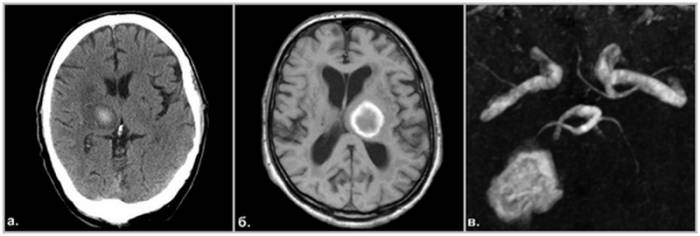

Внутричерепное кровоизлияние — серьезная патология, требующая срочной помощи специалистов. Гематома опасна тем, что нарушает кровоснабжение мозга и повреждает нервную ткань из-за давления. Позднее обращение за медицинской помощью или неадекватное лечение может привести к смещению структур мозга из-за повышения внутричерепного давления, что угрожает жизни. Симптомы могут проявляться не сразу, что приводит к потере времени. При негативной динамике развития кровоизлияния шансы пациента на выживание снижаются, даже при грамотном лечении. Гематома вызывает сильную боль, а с увеличением внутричерепного давления могут появляться тошнота, рвота, нарушения сознания, судороги и очаговые неврологические симптомы (изменение размера зрачков, парезы, нарушения чувствительности, повышенные рефлексы и патологические знаки). Отрицательная динамика может привести к коме, нарушениям сердечно-сосудистой системы и остановке дыхания. Точная диагностика локализации процесса затруднена из-за быстрого изменения объема крови в очаге повреждения после травмы. Основной метод для быстрой оценки состояния мозга — компьютерная томография (КТ). Существуют различные классификации кровоизлияний в зависимости от локализации, источника и сроков. КТ позволяет определить характер гематомы, степень давности и вовлеченность окружающих тканей. Магнитно-резонансная томография (МРТ) помогает выявить тяжелые повреждения аксонов нервных клеток и оценить восстановительные процессы в отдаленные сроки. МРТ также позволяет дифференцировать ишемический и геморрагический инсульты, когда неясно, есть ли гематома в черепной полости.

Визуализация патологического процесса зависит от времени после травмы. В период от 24 до 72 часов после разрыва сосуда гематома может не отображаться на МРТ (ложно отрицательный результат). В первые сутки для оценки масштабов повреждений тканей и костей выполняют КТ, которая позволяет увидеть компоненты черепа и ушибы мозга (контузионно-геморрагические очаги). На основе результатов КТ нейрохирурги принимают решение о необходимости операции. Важна диагностика рентгеновскими лучами кровоизлияний, прошедших 12-72 часа. На КТ хорошо видны смещения костных отломков, их глубина, разрывы сосудов и масштаб вовлечения церебральных структур. МРТ может проводиться в экстренном порядке при госпитализации (например, при геморрагическом инсульте) до 24 часов после происшествия. В других случаях визуализировать кровь на МРТ удается только через три дня. Выявление причин гематом, постановка диагноза и неотложное лечение происходят в стационаре. В частных медицинских центрах МРТ выполняется по назначению врача, что позволяет оценить особенности гематомы (при хроническом процессе), последствия повреждений коры и осложнения, такие как гигрома и рубцово-атрофические изменения. Начиная с 7 суток после разрыва сосуда (в позднем подостром периоде), кровь на МРТ визуализируется лучше, имеет гиперинтенсивный сигнал на Т1 и Т2 взвешенных изображениях. При переходе в хроническую стадию кровоизлияние становится гипоинтенсивным (отображается темными участками).

Визуализация кровоизлияния в головном мозге при магнитно-резонансной томографии (МРТ) зависит от давности патологического процесса. С помощью режимов МРТ — Т1, Т2 и FLAIR (с подавлением сигнала свободной воды) — можно различать разные виды гематом. Их дифференциация основана на сроках геморрагии, поскольку в крови происходят изменения со временем:

• Сверхострая стадия (до 24 часов) — высокий уровень оксигемоглобина и неразрушенные эритроциты. МР-сигнал изоинтенсивный на Т1 и слабо гиперинтенсивный на Т2. В этом периоде МРТ позволяет выявить очаг патологии, но более информативна компьютерная томография (КТ).

• Острое кровоизлияние (1-3 дня) — оксигемоглобин превращается в дезоксигемоглобин. Наблюдается гипо(изо)интенсивный МР-сигнал и выраженный отек мозга. На этой стадии гематому на МРТ не удается рассмотреть.

• Ранний подострый период (3-7 дней) — уменьшение плотности гематомы и ее неоднородность. Гиперинтенсивный сигнал метгемоглобина на Т1 и гипоинтенсивный на Т2. Гематома становится видимой на МРТ.

• Поздняя подострая стадия (7-14 дней) — разрушение эритроцитов и выход метгемоглобина в межклеточное пространство. Гиперинтенсивный МР-сигнал в обеих последовательностях по всему объему кровоизлияния.

• Хронический процесс (от 2 недель) — поглощение макрофагами метгемоглобина приводит к образованию гемосидерина, который выглядит темным по периферии очага на МРТ из-за парамагнитного эффекта железа. Плотность гематомы снижается и становится схожей с мозговым веществом. К концу 30 дней кровоизлияние полностью состоит из гемосидерина и отражается ярким светлым оттенком на Т2 ВИ. Даже спустя годы на исследовании можно обнаружить очаг кровоизлияния из-за скопления молекул оксида железа.

Интенсивность МР-сигнала от гематомы в режиме FLAIR меняется от гиперинтенсивного в первые сутки до гипоинтенсивного при хроническом процессе. На основе отклика от очага повреждения головного мозга на магнитные волны можно определить «возраст» патологии.